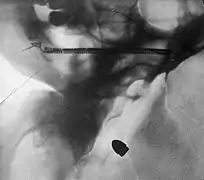

A bullet in the base of a brain, radiograph by Arthur Schuster, c. 1895